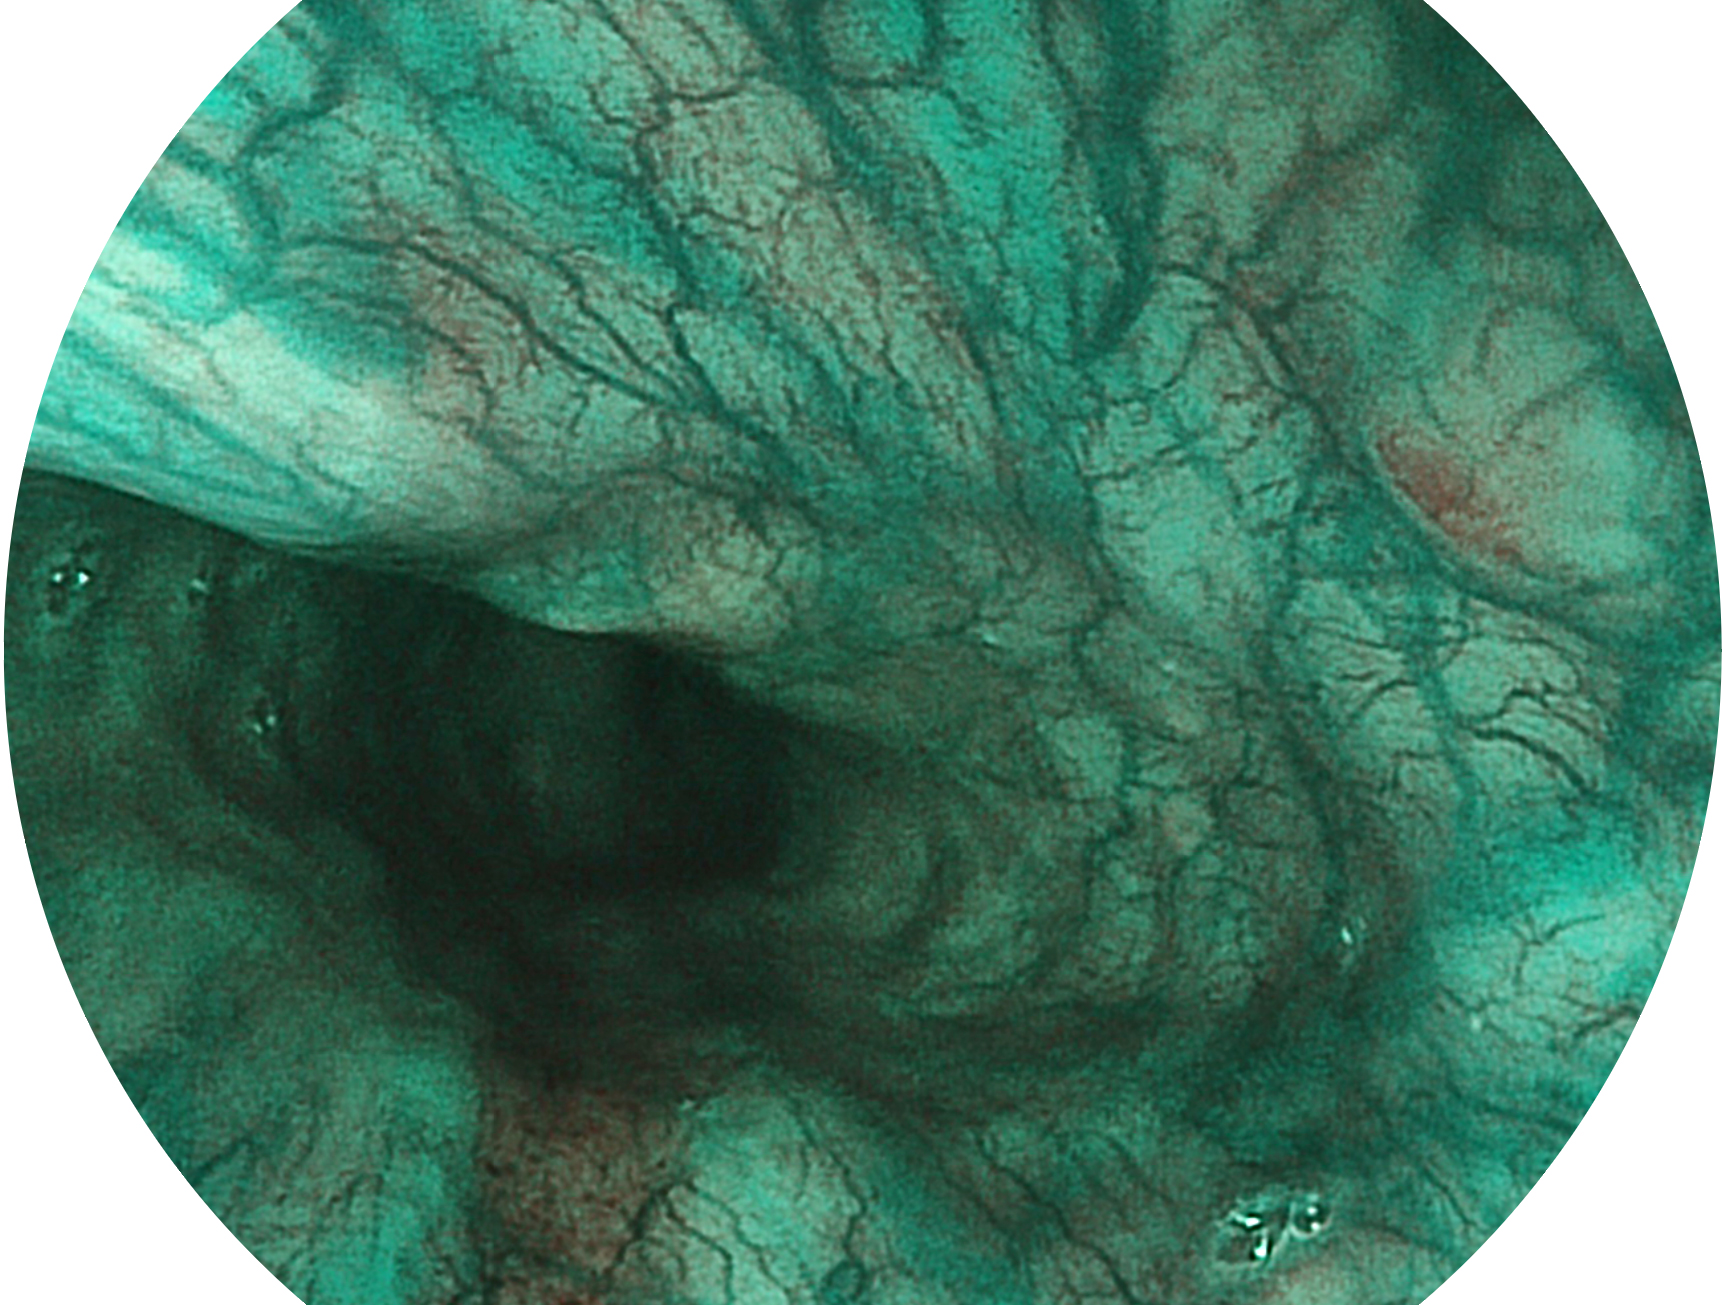

DB中国旗舰官方网站新开发的内镜染色技术,主要是基于多波长LED 光源的开发,VLS-55Q 四波长LED 光源是由四个不同颜色的LED光按照相应照明模式所规定的特定发光比例进行合束后形成,合束后形成的照明光的光谱由红光、绿光、蓝光及蓝紫光这四个不同的波段范围构成。具有更高光谱自由度,通过光谱比例的控制,实现了聚谱成像技术,英文全称为“Spectral Focused Imaging, SFI”,缩写为“SFI”和光电复合染色成像技术,英文全称为“Versatile Intelligent Staining Technology, VIST”,缩写为“VIST”。